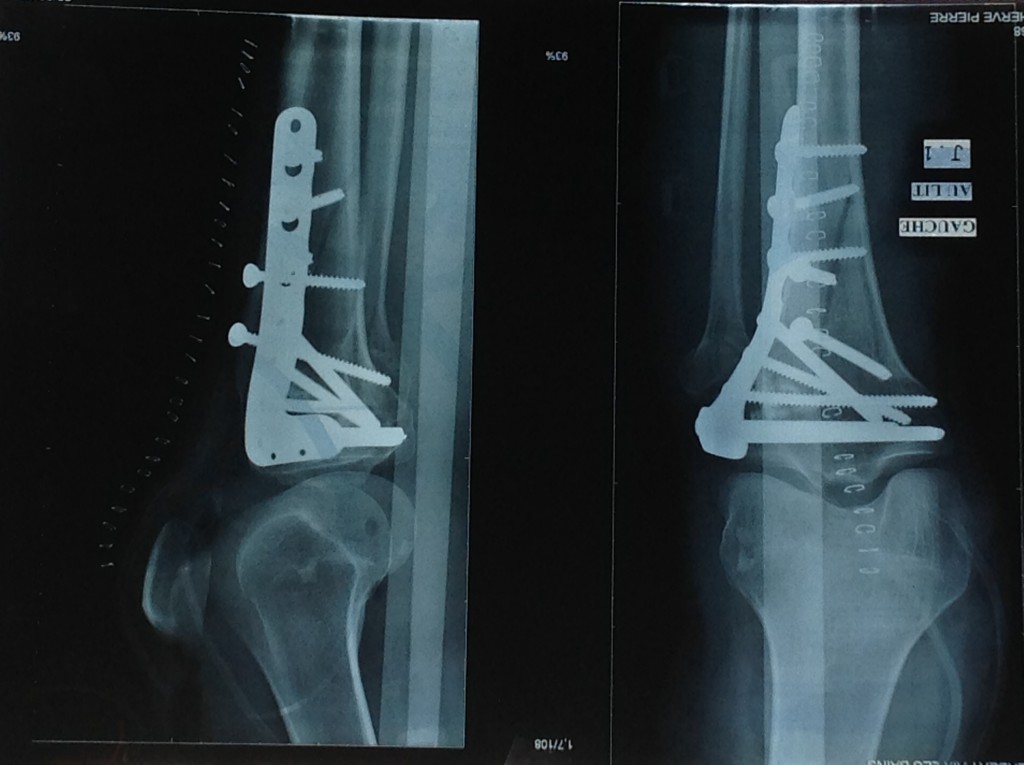

In an incredible three-hour surgery, Dr. Helfet reconstructed my shattered knee cap into no fewer than 20 pieces. Eleven months later, after a flawless recovery, Dr. Helfet and I decided to remove the 10 screws and plate. Once again, he successfully navigated surgery on my genetically fragile bone.